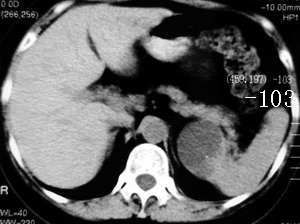

应该为脾脏来源的,囊性肿瘤,从前后ct片显示,有轻度强化改变(ct值),但好像有快速消退的感觉???

ct示脾内缘囊性低密度影,强化后其边缘实质部分与脾同步,且强化程度一样,

考虑脾囊肿

左侧肾上腺受压,病变不是来源于肾上腺,mri脂肪抑制病变为高信号,除外脂肪瘤,考虑来源于脾脏可能性大,强化后壁与脾脏强化基本相似,其内见分隔,囊腺瘤,血管瘤不除外。

cor上显示病灶与肾上腺无关,stir仍呈高信号,增强ct扫描各期均为低密度,且感觉张力较高,还是符合脾脏囊肿性病变的表现。

首先病灶的部位位于脾脏,这一点应该可以达成共识,因为它相邻的实质部分与脾脏同期.同时强化,并可见“鸟嘴”征象。第2:囊性病灶没有明显强化,在延期扫描的时候也是一样。也无病灶缩小的特征。所以我感觉应该考虑:脾脏囊性占位(脾脏囊肿可能性大)